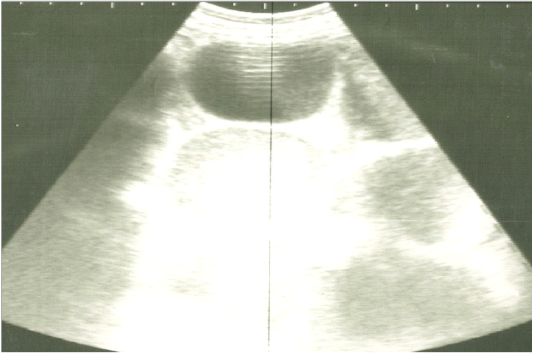

Ultrasonographic image of the left abdomen of horses with colic associated with impaction of the intestine using 3.5 MHz transducer. The intestinal loops were distended with fluid and food particlesand prominent signs of ileus.